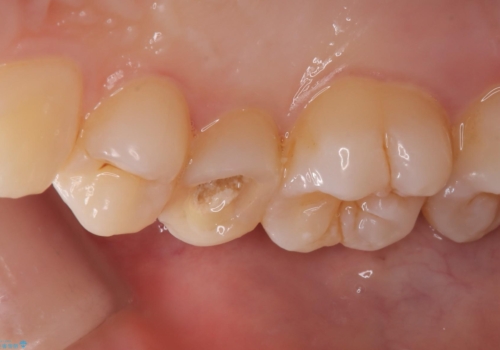

右上5番目の歯が根管治療途中となっており、前医院にて根管が狭く治療が難しいと言われてしまいセカンドオピニオンで当院にいらっしゃいました。

精密根管治療を行うこととしました。

右上5番レントゲン写真上では根管が確認しずらく、根管の狭窄が予想されました。マイクロスコープを使用し、根尖部まで器具を到達させ十分根管洗浄を行うことができました。